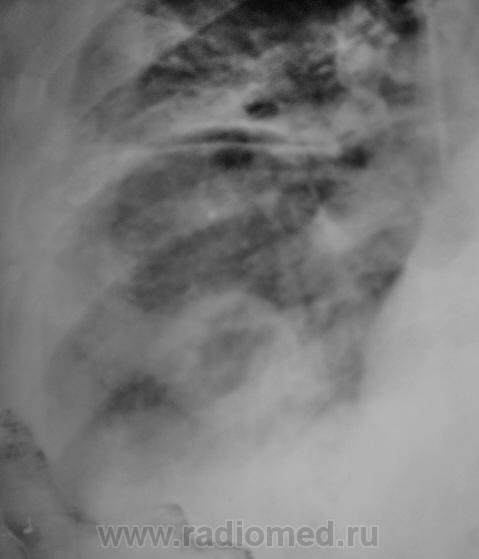

У пациента КТ не на диске, а распечатка. Вот и представляю так. как перефотографировал. Какое мнение будет уважаемые коллеги?

Приложения:

61.Ne_.P4230021a.jpg62.Ne_.P4230022a.jpg63.Ne_.P4230023.JPG64.Ne_.P4230024.JPG65.Ne_.P4230025.JPG66.Ne_.P4230026.JPG67.Ne_.P4230027.JPG68.Ne_.P4230028.JPG

Валентин Львович! Мне думается, что распечатка КТ на бумаге сама по себе уже не информативна и не предназначена для диагностики. Смысла ее перефотографировать абсолютно не имеется.

Но все таки абсцедирующая пневмония!

ИМХО: впечатление о значительной положительной динамике создаётся, на мой взгляд, по причине уменьшения объёма выпота в плевральной полости,вероятно потому, что в последней стоит катетер.Тень абсцесса хоть и стала меньше, но имеет ещё большие размеры.По КТ абсцесс виден и в нижнем поле левого лёгкого; картина самих абсцессов, их множественность, быстрое развитие( через 3 дня после оперативного вмешательства), вызывает подозрение на эмболию легочной артерии( о чём уже говорили коллеги из области).

согласен с ТЭЛА. На КТ подобное видел - субплеврально, полость деструкции с бронхо-сосудистым тяжем к корню легкого, жидкость в плевр полости, быстрая динамика...